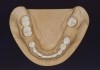

Figure 4. Occlusal contacts occur generally on the posterior teeth, most often on the first molars, followed by the second molars and premolars.

Figure 4